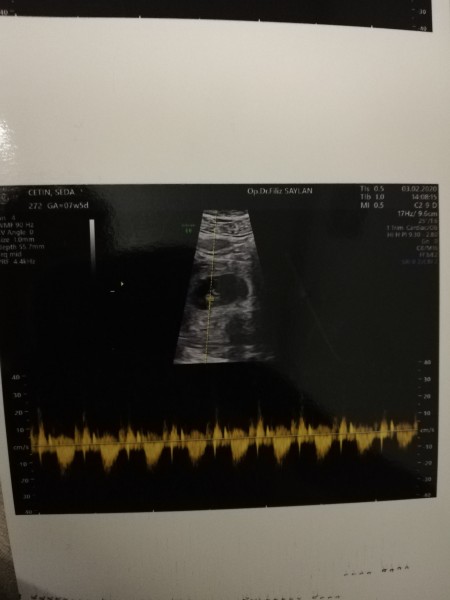

İkiz gebelik mi çok merak ediyorum lütfen yardımcı olun

Kızlar ikiz değilmiş dediğiniz gibi plesentaymış kalp atışlarını duydum yavrumun çok farklı duygu ağladım duyduğum ann Allah kimsenin kucağını boş bırakmasın =)

Gebelik haftası 4+6 çok merak ediyorum ikiz gebelik mi acaba bu durumda olanlar yardımcı olabilir mi

Tek yumurta ikizi gibi duruyor doktor bisey demedimi orda iki tane bebis var gibi bir kesede

Ben ultrason olurken gördüm ama umutlanma ak için soramadım, doktor da kalp atışı duymadan söylemek istemedi sanırım, bizim doktorumuz garanti olmadan hastalarını umutlandırmadan temkinli bir şekilde konuşmayı anlatmayı tercih ediyor. Kalp atışı da 3 şubatta olacak allahın izniyle ama meraktan kendimi alıkoyamıyorum  babaannem 3 tane ikiz doğurmuş bir tanesinin ikiz eşi yaşıyor ama onun sanırım çift yumurta ikiziydi

Yolk kesesi olabilir kesenin içindeki

Ikiz gebeliğe benziyor ama bilemiyorun

Canm daha çok yeni bir geneliğin var o gözüken yolk kesesi. Bebeğin ilk başta ona yapışık gelişicek. Yuvarlak bişey o sadecr iki kenarı gözüküyor

canim onlar bebek degil yolk kesesi zamanla o kuculuyor bebegin buyuyor